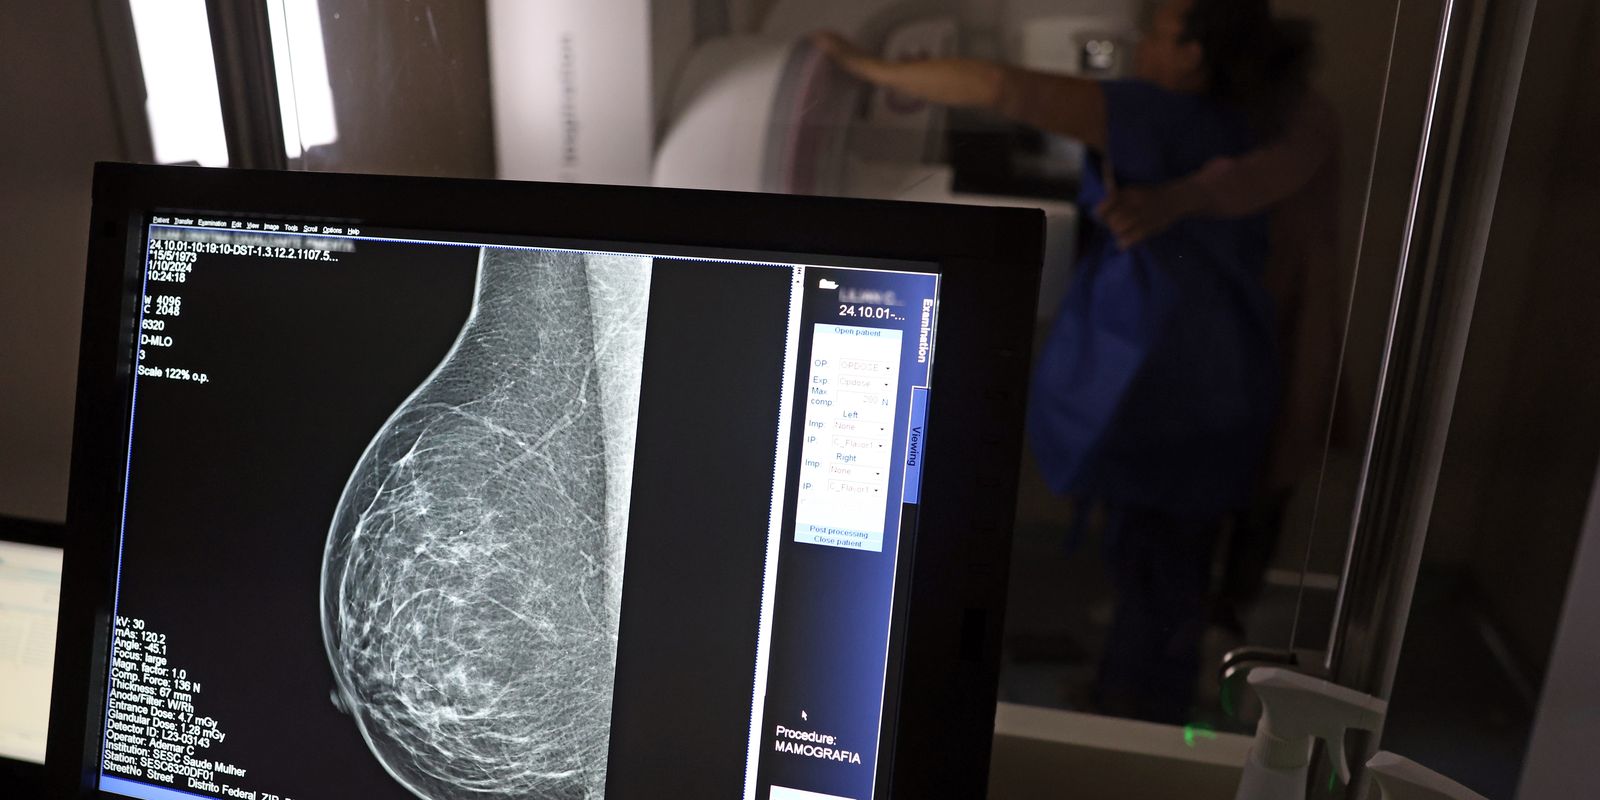

A Advocacia-Geral da República (AGU) informou nesta quinta-feira (20) ter aberto uma ação civil pública contra o médico Lucas Ferreira Mattos, por ele ter dito em postagem nas redes sociais que o exame de mamografia causa câncer de mama.

Mattos, que tem1,3 milhão de seguidores no Instagram e 22 mil do YouTube, fez a declaração em outubro do ano passado, ao responder uma seguidora que o havia questionado sobre o que poderia fazer “pra acabar” com dois nódulos nos seios, que seu médico pessoal havia dito para somente acompanhar com a realização de exames.

“Vamos acompanhar? Acompanhar o quê, se o médico não está fazendo nada para resolver. Ficar fazendo mamografia? Uma mamografia gera uma radiação para a mama equivalente a 200 raio-x. Se aumenta a incidência de câncer de mama por excesso de mamografia. Eu tenho 100% de certeza que seu nódulo benigno é deficiência de iodo”, disse o médico na ocasião, em uma resposta em vídeo.

O caso levou os conselhos regionais de medicina de Minas Gerais e São Paulo a abrirem investigações tendo o médico como alvo. O Instituto Nacional do Câncer (Inca) também informou, à época, não haver evidência de que a mamografia possa causar câncer de mama e que, pelo contrário, o exame previne a doença.

Agora, a AGU pede que o médico seja condenado a pagar R$ 300 mil em indenização por danos morais coletivos, por ter disseminado informação de saúde falsa. O órgão pede ainda que ele seja obrigado a apagar as postagens com a desinformação e a publicar conteúdo pedagógico e informativo sobre a mamografia produzido pelo Ministério da Saúde.

O material deve ser republicado durante a campanha do Outubro Rosa, que ocorre todos os anos para conscientiza sobre a importância do exame preventivo, segundo pede a AGU na ação.

Em nota, a AGU disse que “a propagação de desinformação sobre o tema pode desestimular mulheres a fazerem o exame preventivo, afetando as políticas públicas de enfrentamento ao câncer de mama”.

O órgão anexou ao processo nota técnica do Ministério da Saúde segundo a qual “é recomendado que mulheres de 50 a 69 anos, de risco padrão, façam uma mamografia de rastreamento a cada dois anos. Esse exame pode ajudar a identificar o câncer antes de a pessoa ter sintomas”.